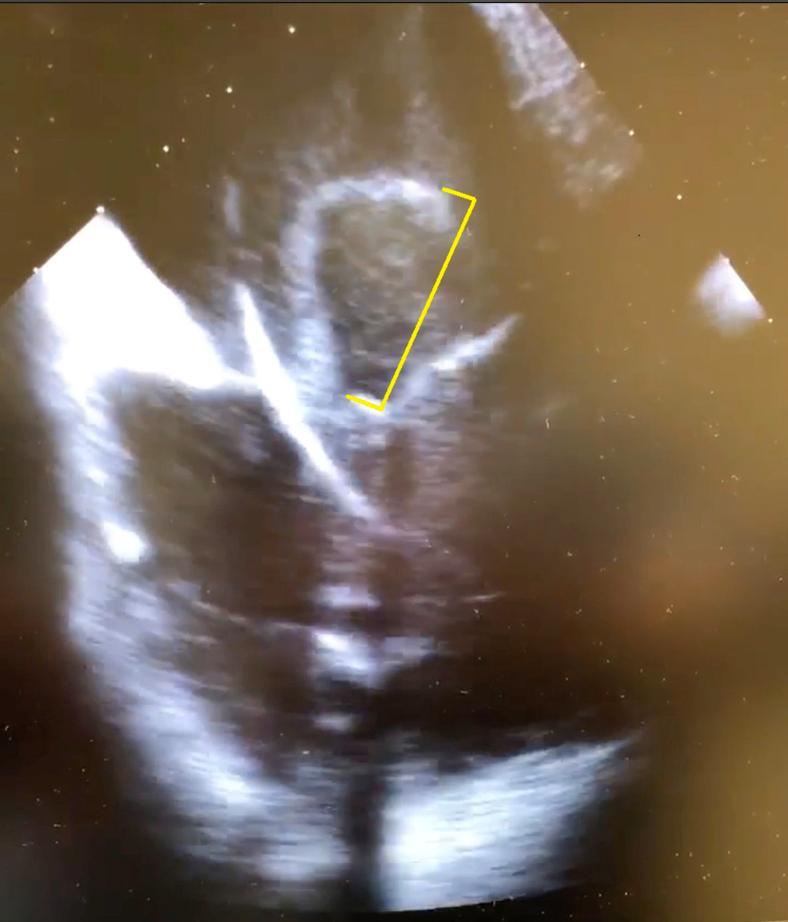

HeartRhythm Case Rep. 2020 Dec 19;7(3):170-173. doi: 10.1016/j.hrcr.2020.12.005. eCollection 2021 Mar.